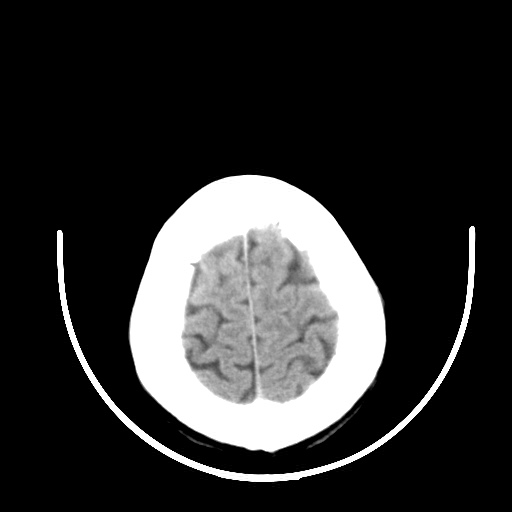

标题: CT16579:女 65岁间断性抽搐. [打印本页]

标题: CT16579:女 65岁间断性抽搐.

作者: zsl6918    时间: 2008-11-11 04:44

老年脑改变

右颞叶软化灶,右基底节区腔隙性脑梗塞;